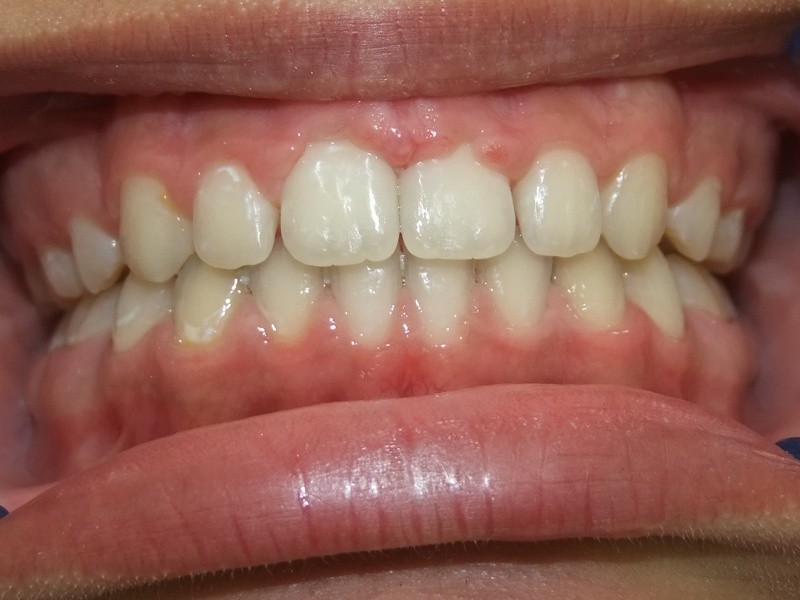

Na behandeling